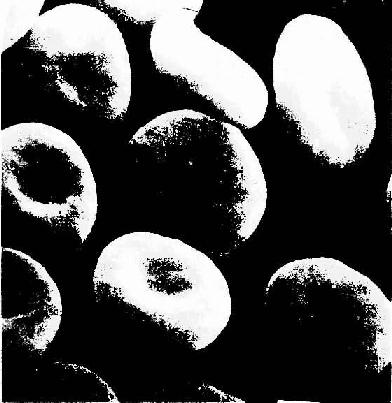

红细胞(erythrocyte,red blood cell)直径7~8.5μm,呈双凹圆盘状,中央较薄(1.0μm),周缘较厚(2.0μm),故在血涂片标本中呈中央染色较浅、周缘较深(彩图5-2)。在扫描电镜下,可清楚地显示红细胞这种形态特点(图5-3)。红细胞的这种形态使它具有较大的表面积(约140μm2),从而能最大限度地适应其功能――携O2和CO2。新鲜单个红细胞为黄绿色,大量红细胞使血液呈猩红色,而且多个红细胞常叠连一起呈串钱状,称红细胞缗线。

图5-3 人红细胞扫描电镜像 ×4800

(白求恩医科大学组织胚胎学教研究室供图)